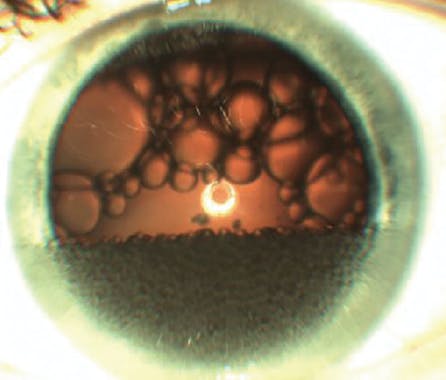

There are several causes of the particulate glaucomas, a term coined by one of us (S.C.). One common etiology is silicone oil emulsification (Figure 1). Silicone oil droplets never absorb; instead, they become embedded in the trabecular meshwork, impeding aqueous outflow, and they often become trapped in the zonules, residual peripheral vitreous, epiretinal membranes, and capsular bag.4

Another type of particulate glaucoma, perfluorocarbon liquid (PFCL) droplet–related glaucoma, occurs if medium-term removal of perfluoro-n-octane is inadequate after its use for inferior retinal detachment or nasal, temporal, and inferior giant retinal breaks.7,8 PFCL often becomes trapped in the zonules, residual peripheral vitreous, epiretinal membranes, and capsular bag (Figure 2).

Figure 2. PFCL droplets in the inferior anterior chamber and posterior to the lens before intraoperative removal of medium-term perfluoro-n-octane.